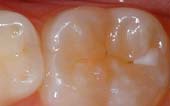

A sealant is a protective coating that is applied to the chewing surfaces (grooves) of the back teeth (premolars and molars), where four out of five cavities in children are found. This sealant acts as a barrier to food, plaque and acid, thus protecting the decay-prone areas of the teeth.

Your pediatric dentist may also recommend protective sealants or home fluoride treatments for your child. Sealants can be applied to your child’s molars to prevent decay on hard to clean surfaces.